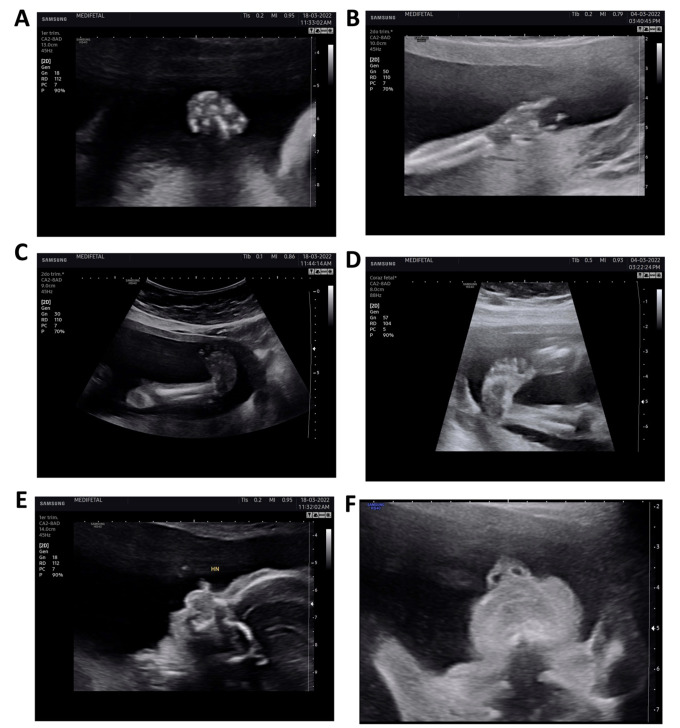

Objectives: To describe a case of prenatal diagnosis of Freeman-Sheldon syndrome based on ultrasound findings and complete fetal exome sequencing.

Materials and methods: A 33-year-old patient currently on treatment for hypothyroidism in whom a 19-week detailed anatomical ultrasound scan showed fetal deformities in more than two body areas (upper and lower limbs), suggesting a diagnosis of arthrogryposis. Genetic counseling was provided and amniocentesis was performed at 20 weeks for fluorescence in situ hybridization (FISH) analysis and complete fetal exome sequencing, with the latter allowing the identification of a heterozygous pathogenic variant of the MYH3 gene which is associated with type 2A distal arthrogryposis.

Conclusions: Complete fetal exome sequencing was a key factor in identifying the MYH3 gene mutation and confirmed that the deformities seen on ultrasound were associated with type 2A distal arthrogryposis. It is important to perform complete fetal exome sequencing in cases of joint malformations seen on prenatal ultrasound.